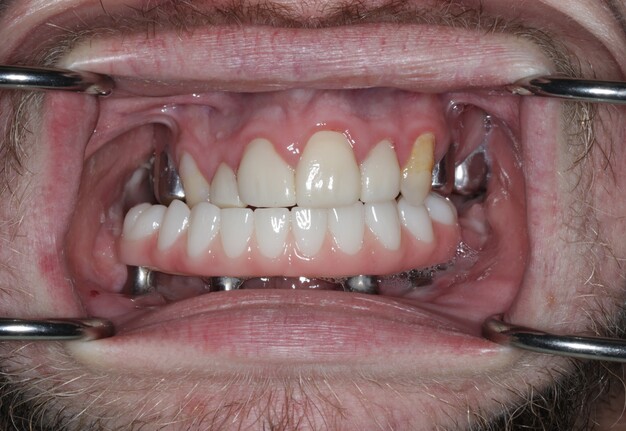

5. Final Prosthesis

The refined prototype was rescanned on the back-pour cast, and a definitive monolithic implant supported fixed zirconia prosthesis was fabricated and successfully delivered (Figs 16 and 17).

Verification of passive seating, which could not be performed radiographically due to the inability to fit x-ray films intraorally, was carried out by visual confirmation on the fabricated physical cast followed by intraoral verification. The full arch implant supported fixed prosthesis was fully seated with no rocking or movement. A high-water design was utilized for enhanced hygiene, eliminating the need for tissue capturing and moulage. Passiveness was verified visually and tactically using a new sharp probe, with no evident gap. A one-screw test was performed to ensure there was no elevation on the opposite end. A screw resistance test was also performed, with all Vortex screws hand-tightened due to the inability to insert a torque wrench intraorally.

The prosthesis was fabricated from multilayered 3Y/5Y zirconia (Ivoclar Vivadent), directly milled without metal Ti-bases, and sealed with Teflon and resin composite. Occlusal contacts were checked, fine refinements were made, and the restoration was polished prior to final insertion.